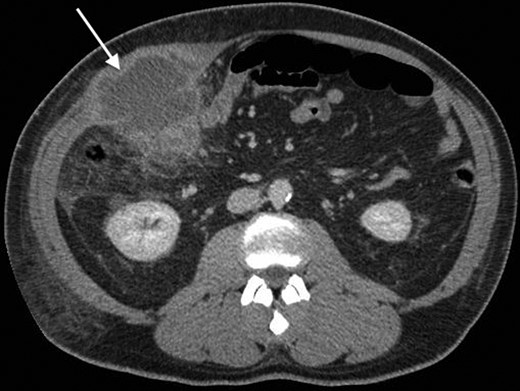

His past surgical history included conservatively managed renal calculi and left inguinoscrotal herniorrhaphy. Right hypochondrial palpation identifying a tender, well-defined, hard, smooth edged, non-pulsatile, non-fluctuant mass (10 × 9 cm). Observations were within normal limits and systemic examinations unremarkable. Haematological results showed the following: albumin 27, WCC 15.7, neutrophils 11.0, CRP 341, amylase 20. Urinalysis, chest and abdominal radiographs (AXR) were normal. Initial resuscitative management was commenced and a contrast enhanced computed tomography (CT) performed. This demonstrated an anterior abdominal wall collection (7 cm) arising from an RUQ appendiceal abscess secondary to acute appendicitis (Figs 1 and 2). Consequent ultrasound (US) guided drainage and pigtail catheter insertion removed 50 ml of frank pus, which isolated pathogens sensitive to penicillin and erythromycin. Following 3 days of intravenous piperacillin and tazobactam (Tazocin®) he was discharged with oral erythromycin. An out-patient barium follow-through and colonoscopy were unremarkable.

An axial CT with contrast showing the RUQ appendiceal abscess.